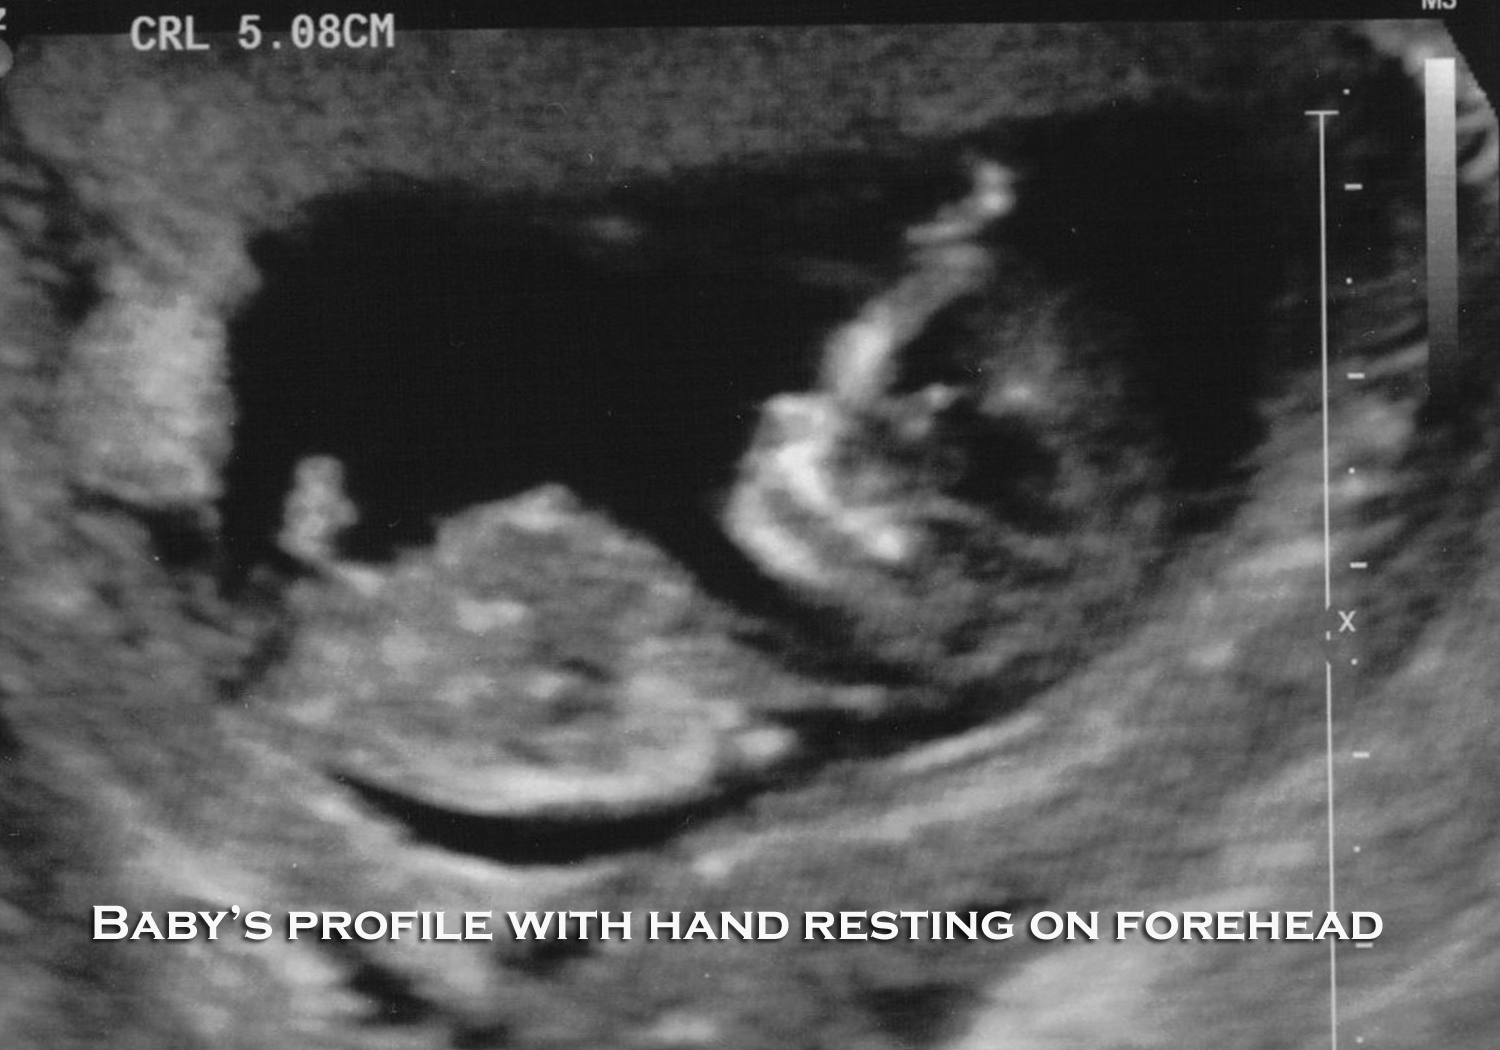

Can You See Boy Parts At 11 Weeks . We broke down what you need to know. By andrea chisholm, md facog. You can't see it, but baby is moving fluidly and gracefully inside your 11 weeks pregnant belly. I had an nucheal ultrasound today. If you're expecting a boy, you might wonder what the ultrasound images will look like. Though sometimes called gender ultrasounds, anatomy scans aren't solely to determine your baby's. Here you can see the head and part of the upper body. You can see the skull bone and the jaw and teeth. At 11 weeks, baby's fingers and toes aren At 11 weeks, the heartbeat can be clearly seen on an 11 week ultrasound scan, pulsing away in your baby’s chest! Between 18 and 22 weeks, you'll get a detailed anatomy scan, called a level 2 ultrasound. Updated on july 1, 2024. The small nose and mouth are clearly visible at the end of the first trimester, even though. I ask the lady if she can peek to see the gender and she did do it really quick but she said. You might be able to see the bladder on an ultrasound at 10 to 14 weeks, and even see the bladder emptying at 15 weeks.

from houseofroseblog.com

It’s just meant to be.

It’s just meant to be. Can You See Boy Parts At 11 Weeks You can see the skull bone and the jaw and teeth. You can't see it, but baby is moving fluidly and gracefully inside your 11 weeks pregnant belly. Between 18 and 22 weeks, you'll get a detailed anatomy scan, called a level 2 ultrasound. Updated on july 1, 2024. We broke down what you need to know. The small nose. Can You See Boy Parts At 11 Weeks.